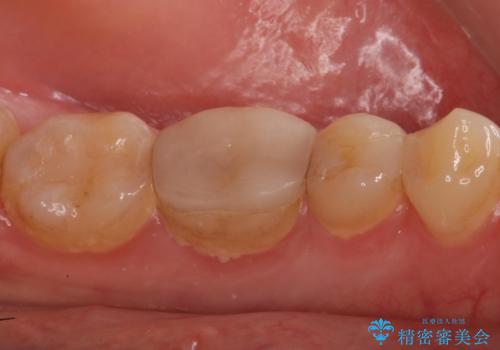

歯の高さがなく、またセラミックアンレーは割れるリスクが高いため、セラミックのアンレーとはせず、クラウンとし、さらに割れにくいようにヴェレッツァクラウンとしました。

- 合計 17.6万円(内訳 左下7:e-max インレー 7.7万円、左下6:セラミッククラウン(ヴェレッツア 8.8万円)、仮歯 1.1万円)費用は治療当時の料金となります